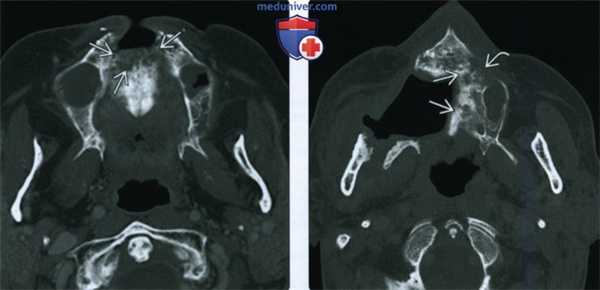

(Слева) При аксиальной КТ в костном окне у пациента, получавшего лучевую терапию по поводу плоскоклеточного рака носовой перегородки, визуализируется очаг литического характера в передних отделах верхней челюсти, представляющий собой треугольный участок деструкции костной ткани.

(Справа) При аксиальной КТ в костном окне у другого пациента определяются признаки выполненной резекции неба справа, а также изменения смешанного (склеротического и литического) характера в верхней челюсти слева, которая подвергалась облучению. Верхняя челюсть является относительно устойчивой к ионизирующему излучению, в ней редко возникает остеорадионекроз. Лучевые признаки идентичны таковым при поражении других костей лицевого скелета и основания черепа.

(Слева) При аксиальной КТ с КУ определяется остеорадионекроз нижней челюсти справа, осложненный инфицированием жевательного пространства. Определяется также нарушение целостности кортикальной пластинки и диффузный, выраженный отек жевательных мышц и околоушной слюнной железы, расширение ее выводного протока, заполненного дебрисом воспалительного характера.

(Справа) При МРТ Т1ВИ в корональной проекции определяется диффузное замещение сигнала, в норме наблюдающегося в костном мозге, и характерного для жира. Пристствуют множественные участки нарушения целостности кортикальной пластинки. Индурация и отек подкожных тканей являются часто встречающимися изменениями при остерадионекрозе нижней челюсти.